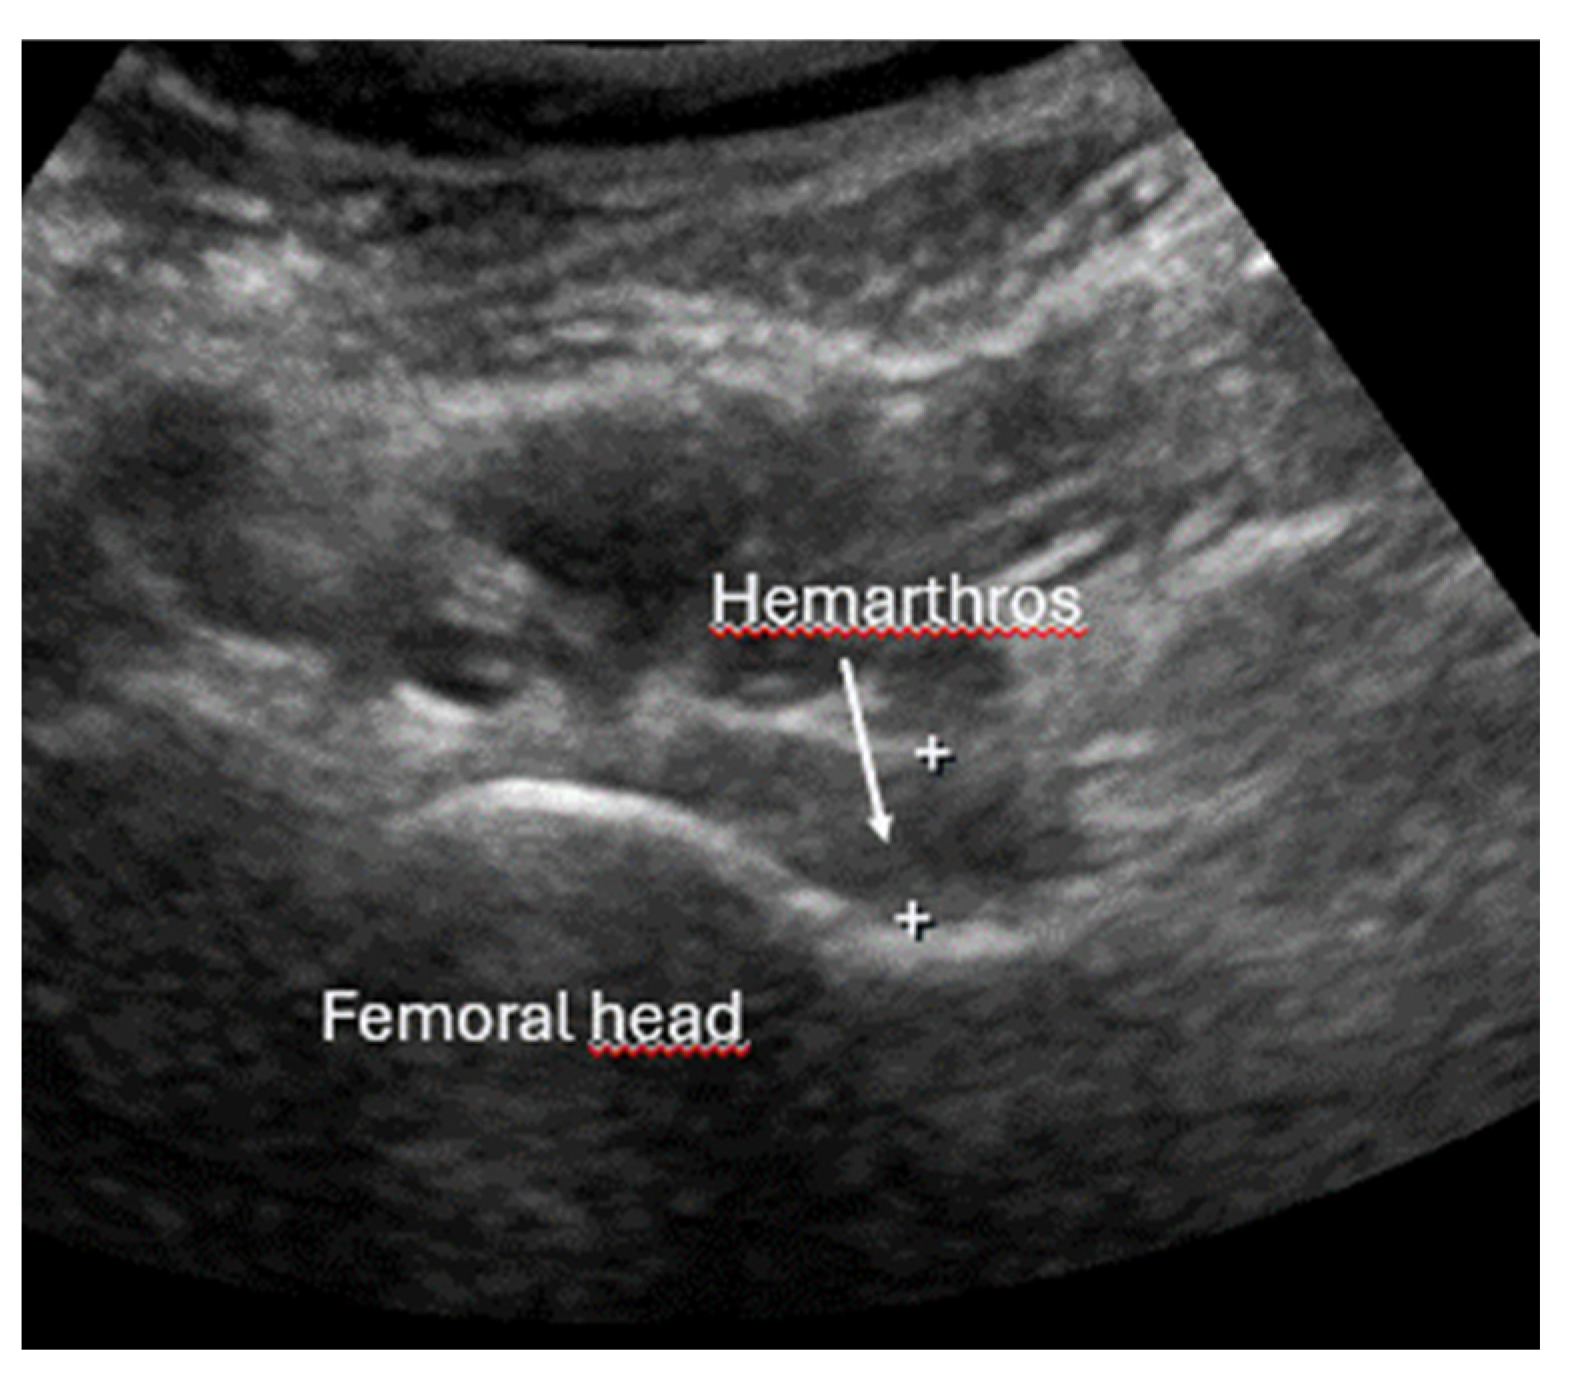

- Local hematoma or soft tissue edema: fluid collections or increased echogenicity near the fracture site indicating bleeding and inflammation.

- Joint effusion and liphemarthrosis: fluid accumulation within a joint, sometimes containing fat droplets, which often indicates an intra-articular fracture.

- Safran, O.; Goldman, V.; Applbaum, Y.; Milgrom, C. Posttraumatic painful hip: Sonography as a screening test for occult hip fractures. J. Ultrasound Med. 2009, 28, 1447–1452. [Google Scholar] [CrossRef]